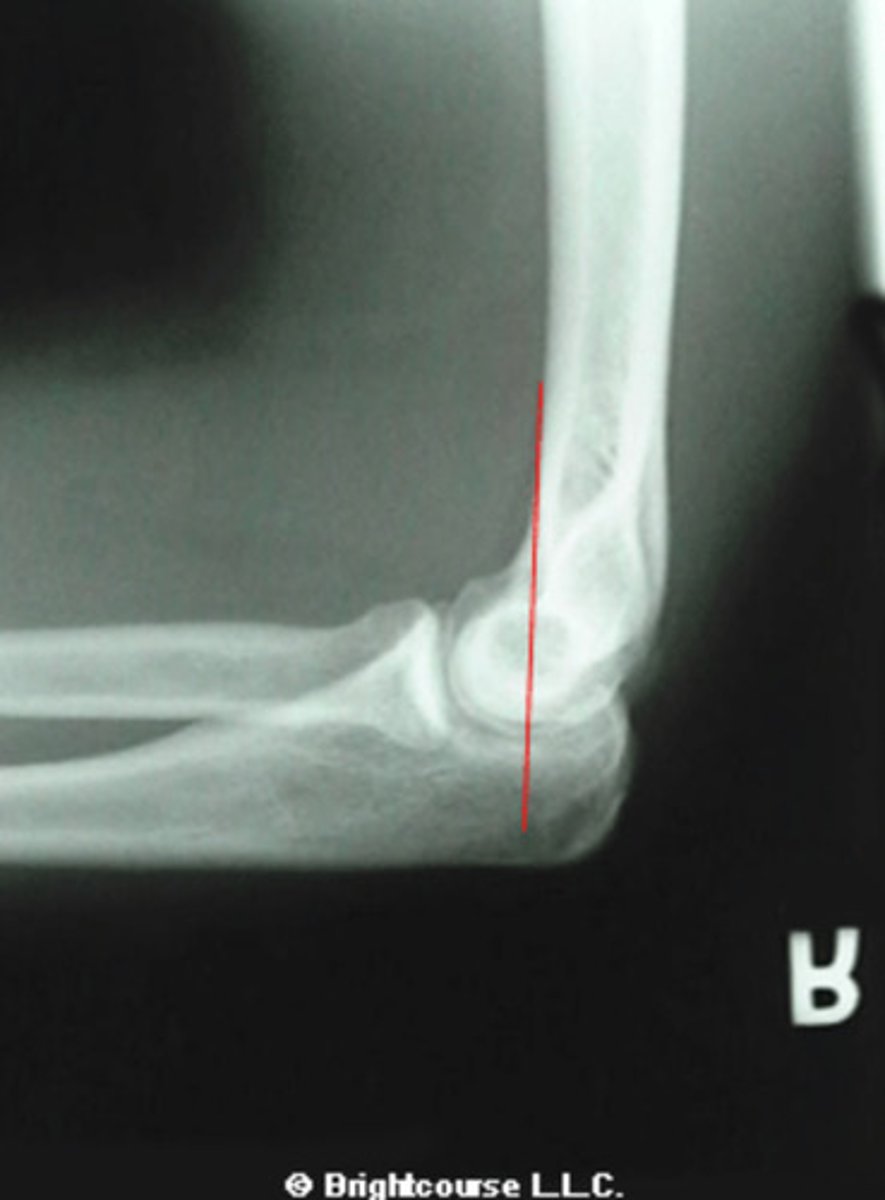

Lateral elbow

What is the name of the radiographic projection?

Anterior humeral line

What line is being drawn in this image?

Through the Capitellum

What is the normal measurement for the anterior humeral line?